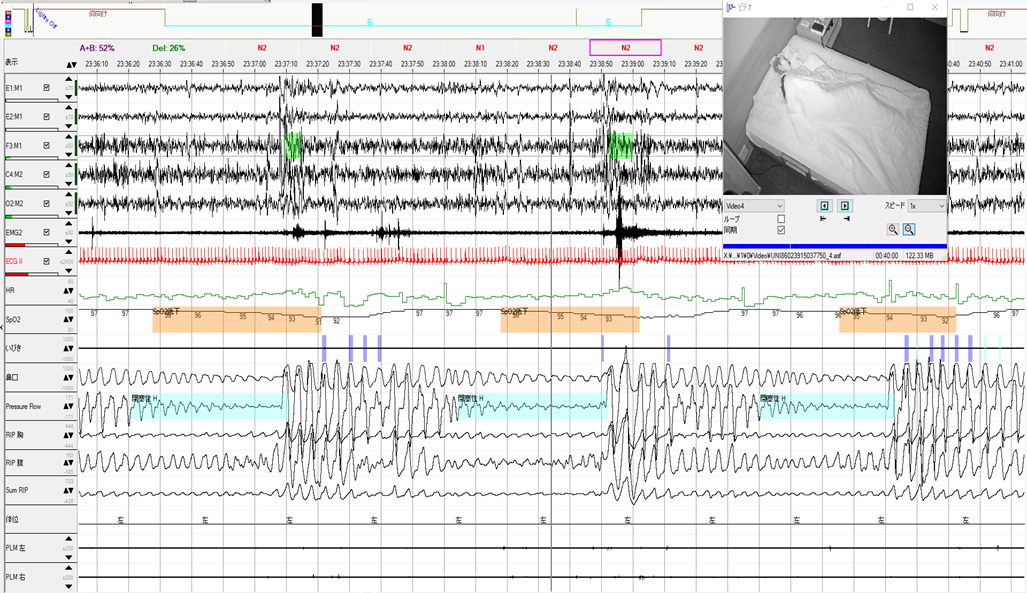

BMIが低値でも仰臥位では重症の無呼吸症例

50歳台 女性 身長:156㎝ 体重:45kg BMI18.5 ESS:4 健診で不整脈を指摘され、静脈瘤、下腿浮腫の症状で来院されました。ホルター心電図でCVHRが23回/時間の結果で、さらにいびきの指摘もあり、簡易検査を施行したところREI=13.4回/時間、最低SpO2=88%、2%ODI=25.2回/時間でした。CVHRはAHIとの相関が報告されてお…